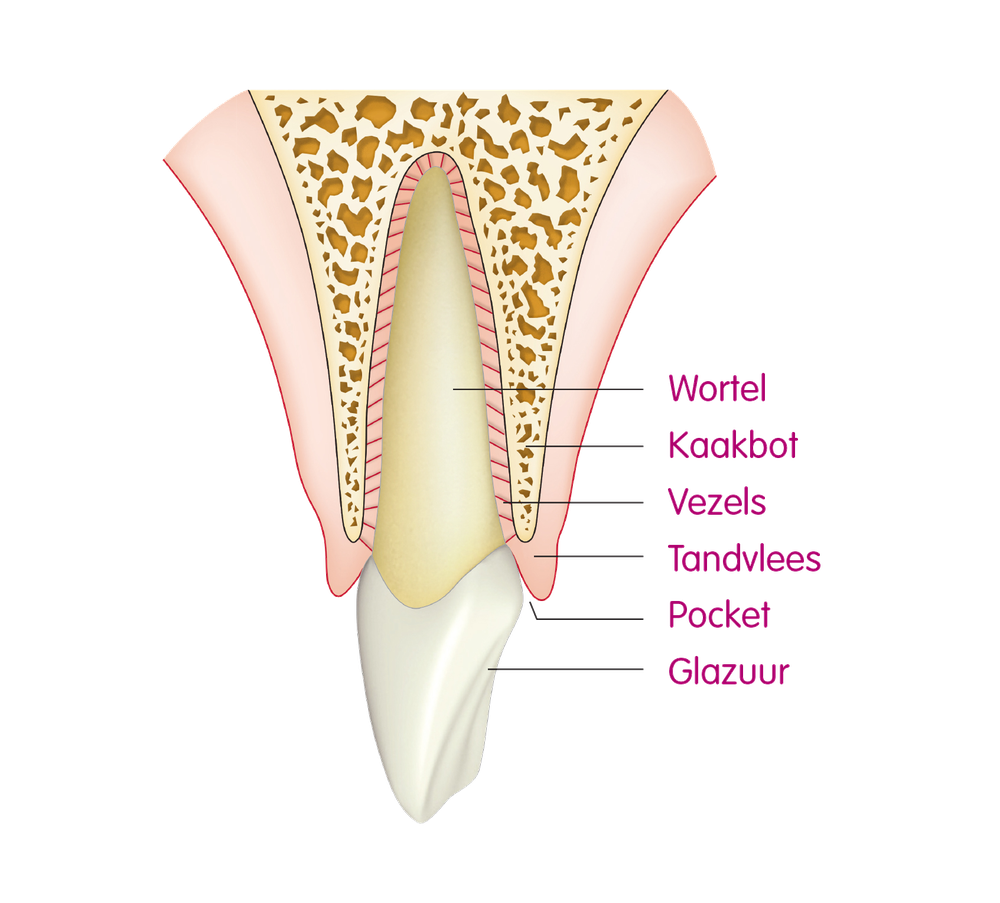

tandvleesontsteking Tandarts.nl

Tandvlees Tandheelkundig centrum Molenvliet

Gezwollen tandvlees is een toestand waarbij het tandvlees opgezwollen is. Dit kan worden veroorzaakt door tandplak, gingivitis ( ontsteking van het tandvlees), of een andere onderliggende aandoening. Raadpleeg je tandarts voor een correcte diagnose en passende behandeling.

Ontstoken tandvlees

Een bult op het tandvlees wordt ook wel een fistel of pijpzweer genoemd. De meest voorkomende oorzaak van een fistel in de mond is een ontsteking onder het tandvlees. Bij deze ontsteking kan pus ontstaan, wat zich vervolgens kan uitbreiden tot een puskanaal door het tandvlees, en soms zelfs door de tanden zelf.

Wat is het? Een tandabces is een etterophoping die ontstaat is in een afgesloten holte in ontstoken tandvlees of een ontstoken tandwortel. Het tandvlees vormt de buitenste bekleding van de tand. In de tandwortel zitten de zachte weefsels, bloedvaten en tandzenuwen.